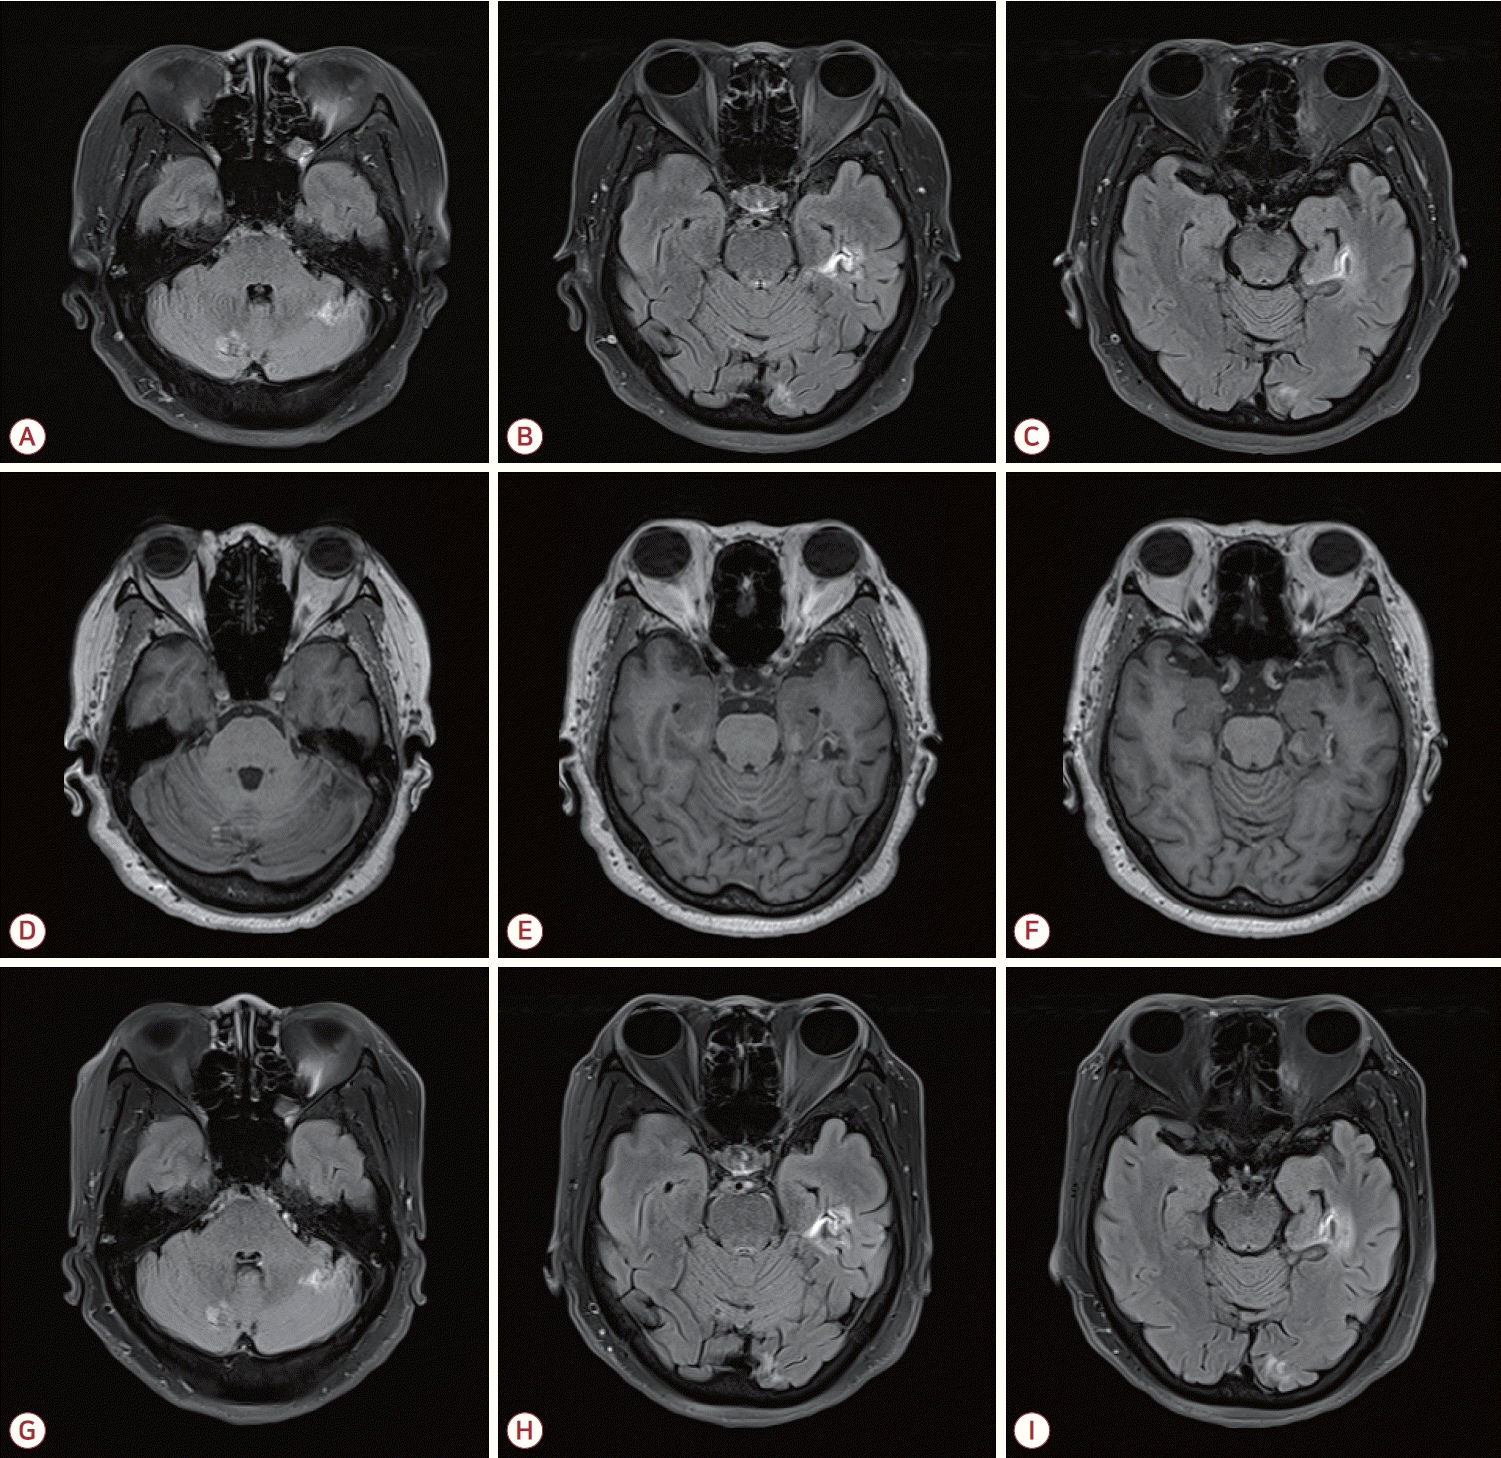

환자는 6년 학력이었으며 2024년 8월에 시행된 서울신경 심리선별종합검사(Seoul Neuropsychological Screening Battery, SNSB) 결과 기억력, 전두엽기능 그리고 시공간 인지기능의 저하 소견을 보이는 다영역, 기억상실형 경도인지장애(amnestic mild cognitive impairment [MCI], multiple domain) 상태였다. 간이정신상태 검사(mini-mental state examination, MMSE) 점수는 25점, 임상치매평가척도(clinical dementia rating, CDR)는 0.5단계, CDR-sum of box (SB)는 2.5점이었다. SNSB-dementia version (SNSB-D)의 종합 점수(composite score)는 106점이었다. 2024년 8월 시행된 뇌MRI에서 좌측 해마(hippocampus)와 해마곁이랑(parahippocampal gyrus), 좌측 후두엽(occipital lobe), 양측 소뇌(cerebellum)에서 만성 뇌경색 소견을 보였으며 뇌MRA는 정상이었다(Fig. 2-A-F). 심전도와 24시간 홀터 검사 소견은 정상이었다. 환자에게 아스피린과 뇌활성화제를 처방하였으며 뇌 병변의 변화를 확인하기 위하여 2025년 5월 뇌MRI를 재시행하였고 특별한 변화는 없었다(Fig. 2-G-I). 2025년 5월에 시행된 SNSB 검사상 기억력, 집중력 그리고 시공간 인지기능의 저하 소견을 보이는 amnestic MCI, multiple domain 상태였으며 MMSE 점수는 25점, CDR은 0.5단계, CDR-SB는 2.5점이었다. SNSB-D의 종합 점수는 138점으로 전반적인 인지기능의 호전 소견을 보였다(Fig. 3).

Figure 2.

MRI at the time of diagnosis of vascular cognitive impairment secondary to MPO-ANCA-associated vasculitis demonstrates hyper-intensities in both cerebellar hemispheres (A) and the left parahippocampal and occipital gyri (B-C) on FLAIR images, with corresponding hypo-intensities in the same regions on T1-weighted images (D-F). Follow-up FLAIR images obtained 8 months later (G-I) show no interval change. MRI; magnetic resonance imaging, MPO; myeloperoxidase, ANCA; antineutrophil cytoplasmic antibody, FLAIR; fluid attenuated inversion recovery.